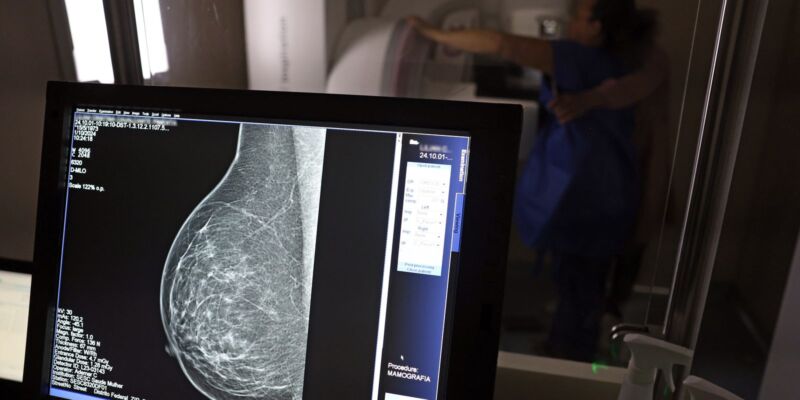

O Ministério da Saúde passou a recomendar o acesso a mamografia, via Sistema Único de Saúde (SUS), para mulheres de 40 a 49 anos – mesmo que não haja sinais ou sintomas de câncer de mama. De acordo com a pasta, a faixa etária concentra 23% dos casos da doença, e a detecção precoce aumenta as chances de cura.

Até então, a orientação era que o exame fosse feito a partir dos 50 anos.

A medida faz parte de um conjunto de ações anunciadas nesta terça-feira (23) voltado para a melhoria do diagnóstico e da assistência. A recomendação para mulheres a partir dos 40 anos é que o exame seja feito sob demanda, em decisão conjunta com o profissional de saúde.

As mamografias via SUS em pacientes com menos de 50 anos, de acordo com a pasta, representam 30% do total, o equivalente a mais de 1 milhão apenas no ano de 2024.

Outra medida anunciada é a ampliação da faixa etária para o rastreamento ativo – quando a mamografia é solicitada de forma preventiva a cada dois anos. A idade limite, até então, era 69 anos. Agora, passa a ser 74 anos. Dados do ministério revelam que quase 60% dos casos de câncer de mama estão concentrados entre 50 e 74 anos.

“A ampliação do acesso à mamografia aproxima o Brasil de práticas internacionais, como as adotadas na Austrália, e reforça o compromisso em garantir diagnóstico precoce e cuidado integral às mulheres brasileiras. O câncer de mama é o mais comum e o que mais mata mulheres, com 37 mil casos por ano”, reforçou a pasta.

Os números mostram que, em 2024, cerca de 4 milhões de mamografias para rastreamento e 376,7 mil exames diagnósticos foram realizados no SUS.